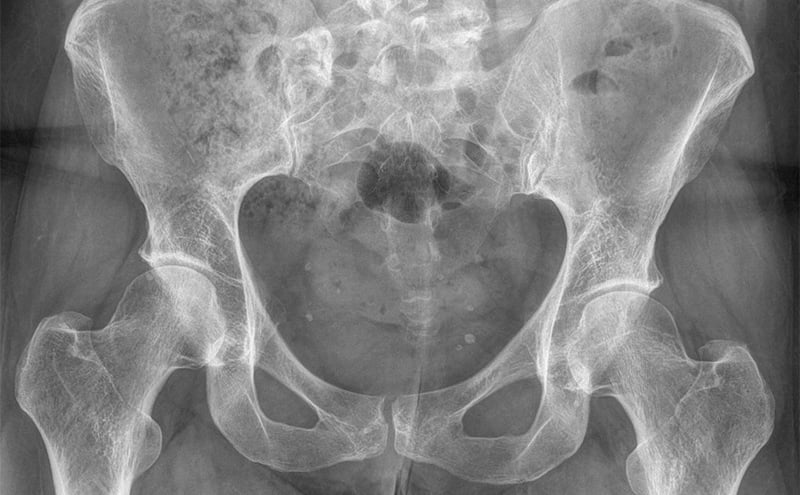

While her films did not demonstrate any signs of spondylolysis/thesis, she did have an abnormal finding of elongation and protuberance of the right transverse process at L5, which was superiorly located compared to the left L5 transverse process with associated pseudoarticulation with the iliac crest.  This was in the exact location of her discomfort.  Patient was made aware of these findings and was given a Medrol dose pack for inflammation of the arthritic changes occurring at the pseudarthrosis site.  Patient was given a referral to neurosurgery for follow up.

Bertolotti’s syndrome (BS), also known as lumbosacral transitional vertebra, was first described by Dr. Mario Bertolotti in 1917.  It is characterized by the presence of a variation in L5 with a large transverse process which is either articulated or fused with the sacrum or, less commonly so, the iliac crest.  This can produce a chronic, persistent lower back pain.  The discomfort can be intermittent secondary to arthritic exacerbations around the pseudoarticulation.  This syndrome affects approximately 4-8% of the population and is an important cause of low back pain in younger patients, many of which will be incorrectly diagnosed with sacroiliitis. Most patients with this syndrome present in their 20’s and 30’s; however, some, like our patient, may present later as arthritic changes occur.

For a patient with chronic low back pain with TTP just lateral to the spine and no prior imaging, a plain radiograph of the lumbar sacral spine is all it takes for diagnosis.  Treatment for Bertolotti’s syndrome includes interventions such as local anesthetic with steroid injection into the pseudoarticulation, physical therapy, or resection of the accessory joint if conservative treatment fails.  While our patient did not have radicular pain, it is not uncommon to have sciatica as the adjacent L5 nerve root can become irritated.